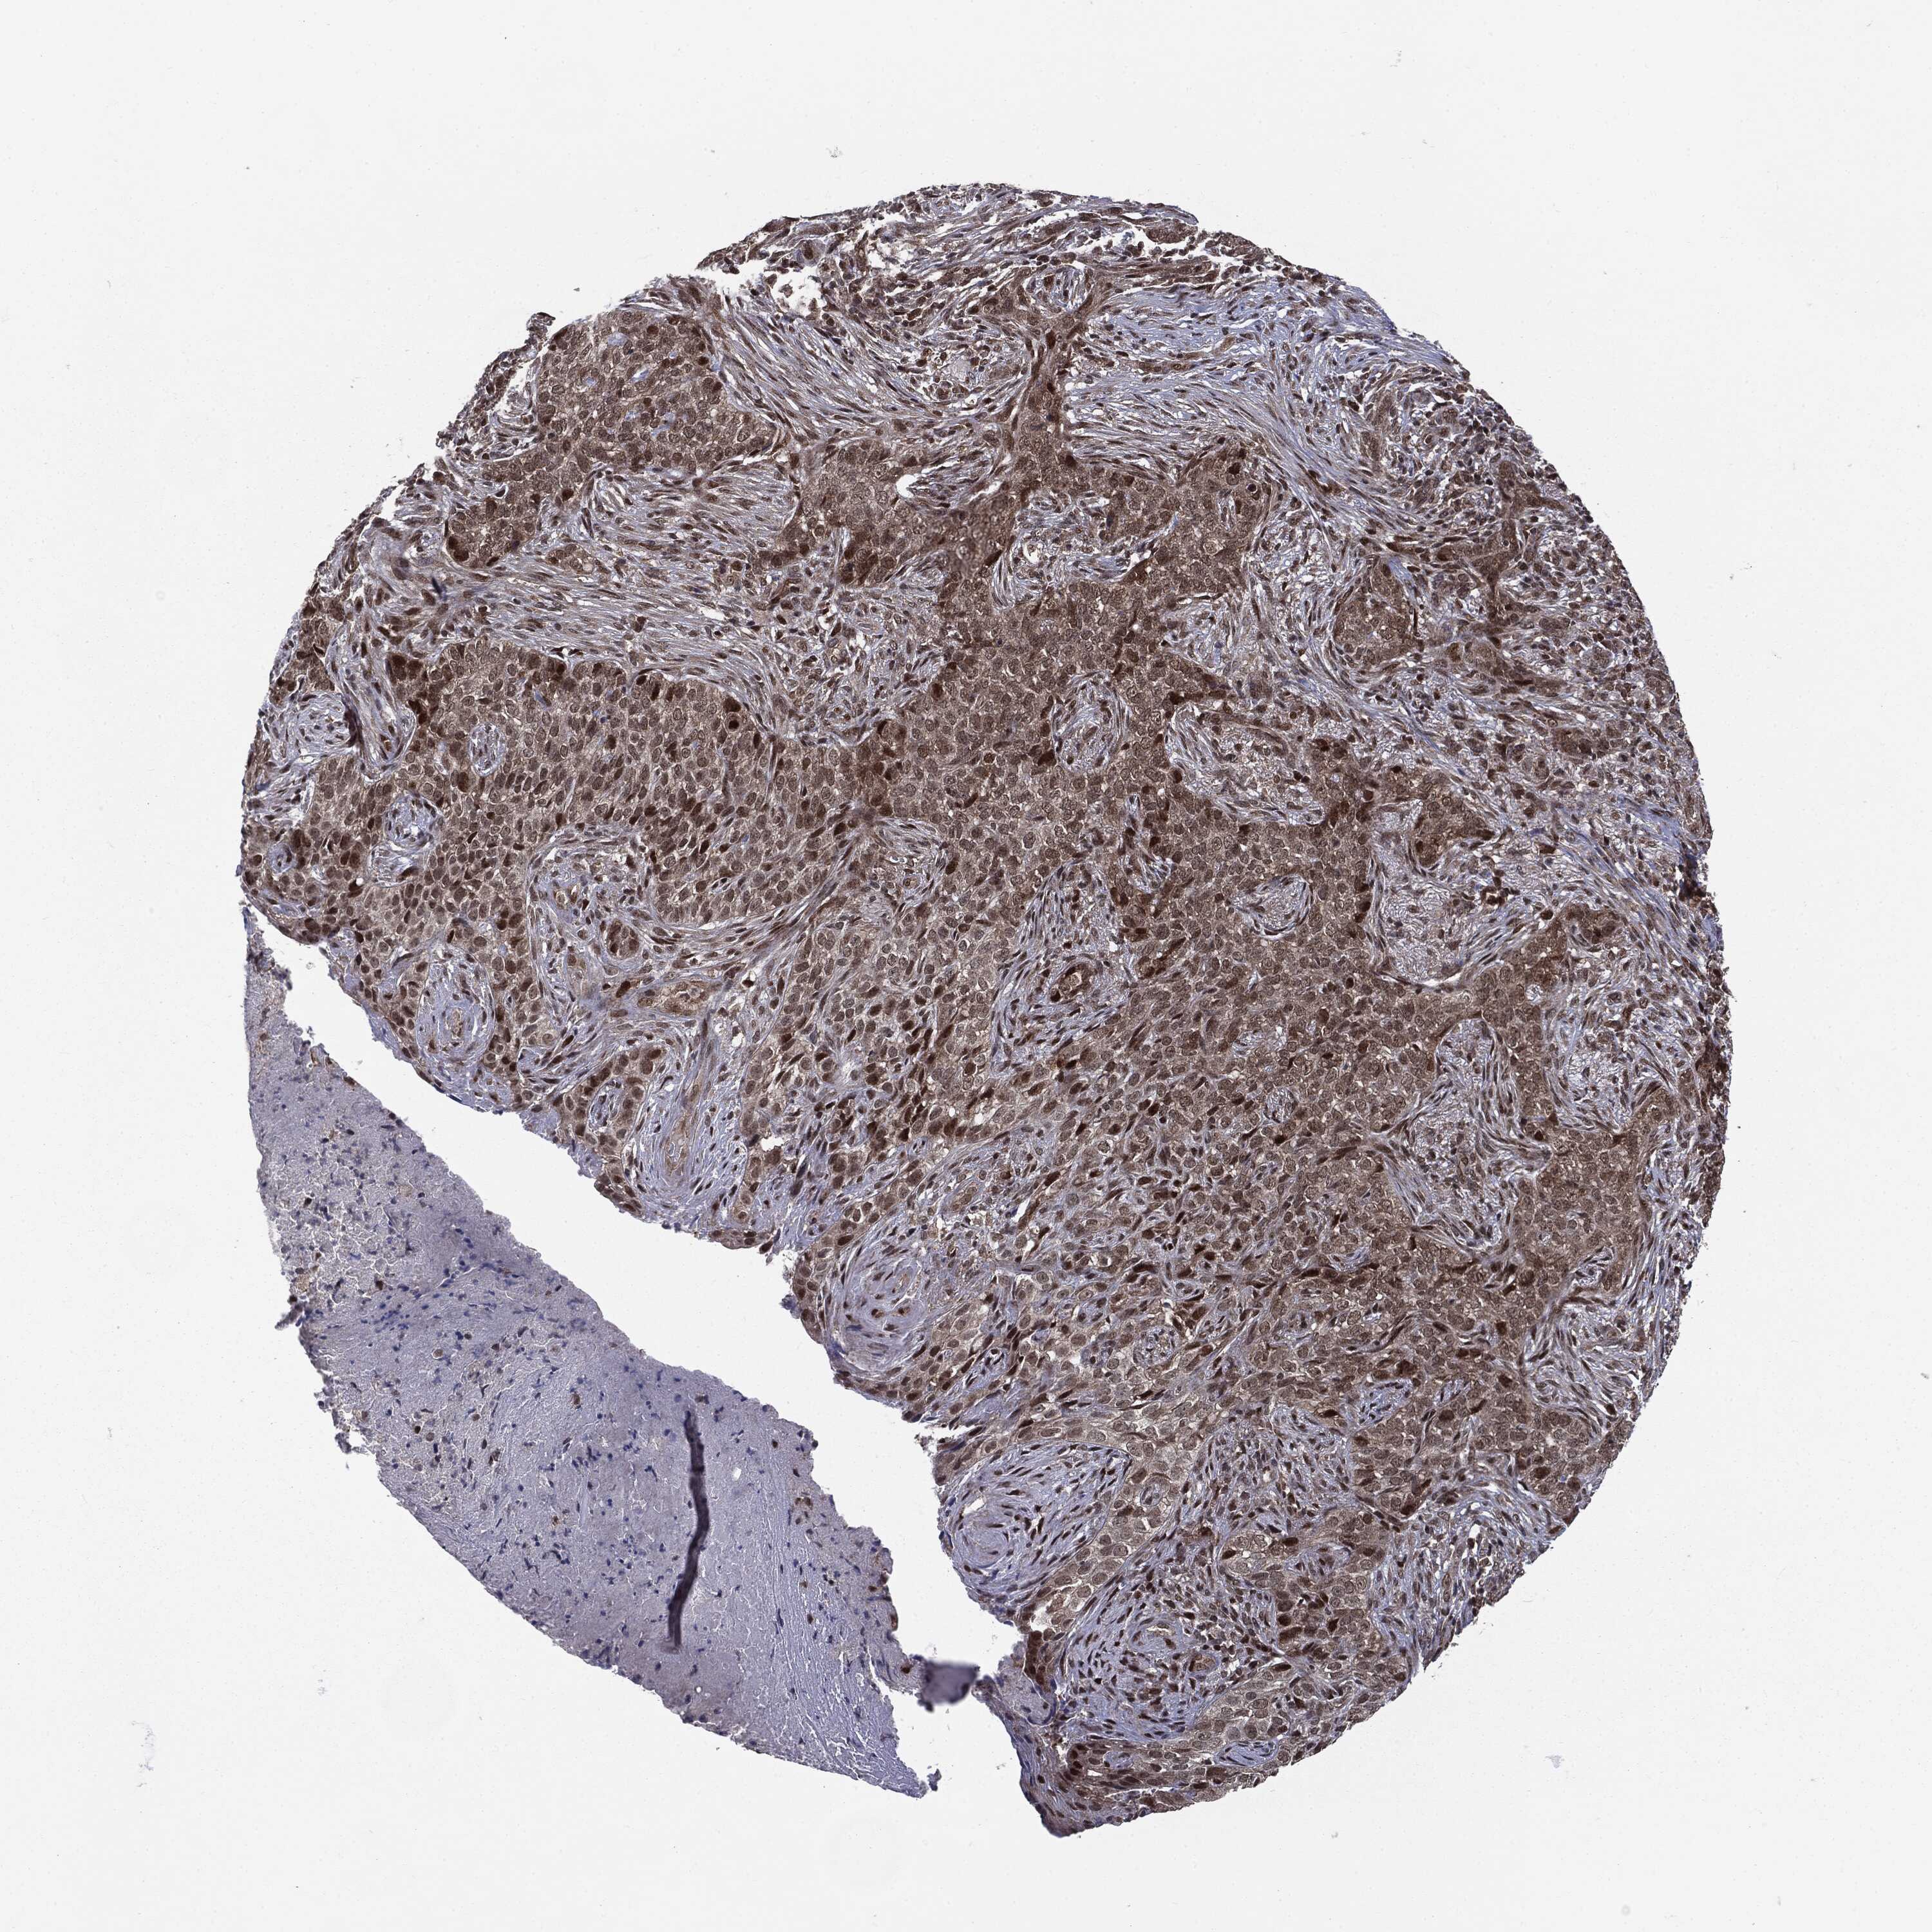

SKIN CANCER - Protein expressioni

A mouse-over function shows sample information and annotation data. Click on an image to view it in a full screen mode. Samples can be filtered based on level of antibody staining by selecting one or several of the following categories: high, medium, low and not detected. The assay and annotation is described here.

Antibody stainingi

Antibody staining in the annotated cell types in the current human tissue is reported as not detected, low, medium, or high, based on conventional immunohistochemistry profiling in selected tissues. This score is based on the combination of the staining intensity and fraction of stained cells.

Each image is clickable and will lead to virtual microscopy that enables deeper exploration of all samples and also displays staining intensity scores, fraction scores and subcellular localization as well as patient and tissue information for each sample.

CAB035999

Squamous cell carcinoma, NOS